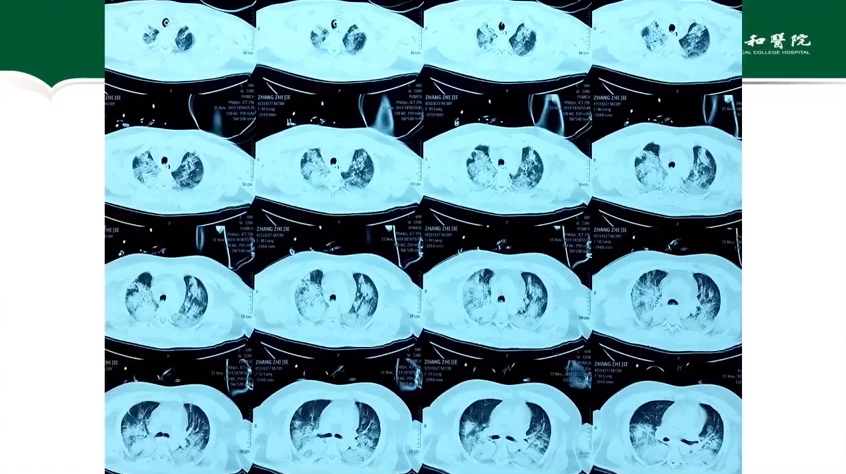

魏俊吉教授:神经急重症患者的颅内压管控

讲题:神经急重症患者的颅内压管控